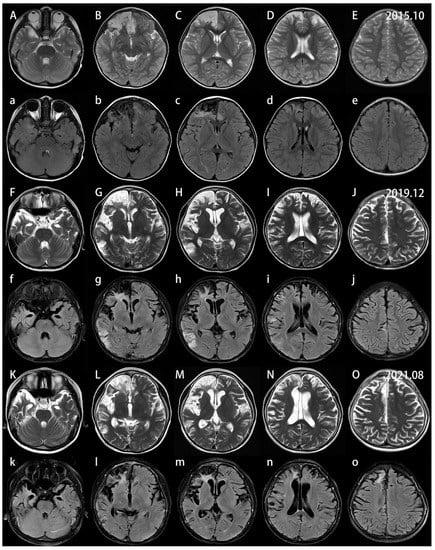

2. Case Report